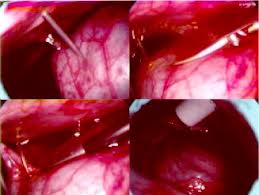

Tale fenomeno comporta una compressione del cuore e delle sue cavità, impossibilitate a contrarsi regolarmente e a distendersi per raccogliere il sangue refluo. Si determina così una situazione di grave insufficienza cardiocircolatoria acuta, con scompenso cardiaco, riduzione della portata, ipotensione e, nelle forme più severe, arresto cardiocircolatorio totale. Il liquido che si va ad accumulare nello spazio pericardico può essere sieroso, infiammatorio (come nella pericardite infettiva o uremica) o sangue (nelle forme traumatiche o con fissurazione della parete miocardica nel corso di infarto). Il tamponamento cardiaco si evidenzia quando tale raccolta avviene all’improvviso, senza che i foglietti del sacco pericardico abbiano la possibilità di distendersi in maniera progressiva adattandosi alla nuova situazione: in queste condizioni sono sufficienti poche decine di millilitri di fluido per scatenare una sindrome compressiva. La diagnosi clinica, oltre che sull’esame obiettivo, viene fatta su indagini radiologiche (con allargamento marcato del profilo dell’ombra cardiaca) ed ecografiche (con dimostrazione diretta della presenza di liquido di versamento pericardico). La terapia d’elezione consiste nella pronta evacuazione della raccolta liquida tramite puntura del sacco pericardico (pericardiocentesi) a scopo decompressivo; nelle forme recidivanti, è pertanto utile la messa in sede di un sottile catetere per permettere successivi svuotamenti nel tempo.

La cura consiste nello svuotamento del sacco pericardico mediante pericardiocentesi. Nel momento del versamento pericardico il trattamento da effettuare varia a seconda se il tamponamento sia presente o comunque minacciato, oppure non vi sia l’immediata minaccia. Quando il tamponamento è minacciato è comunque meglio agire tramite idratazione endovenosa, in casi più gravi è necessario aggiungere la somministrazione di sostanze come la dobutamina o la dopamina; questi trattamenti devono essere usati senza escludere il trattamento primario: la pericardiocentesi. Di solito questa pratica viene utilizzata nella modalità chiusa (tramite accesso subxifpodeo attraverso una guida ecocardiografica, dove il chirurgo opera e visualizza sullo schermo le sue azioni). Più sicuro è comunque l’utilizzo del drenaggio chirurgico (effettuato attraverso la pericardiocentesi aperta), dove spesso grazie alla creazione di una finestra pericardica si possono evitare nuovi episodi successivi. Appena sottratti i primi liquidi in eccesso si denota un miglioramento nella persona. In caso di attacchi continui e frequenti si può effettuare la scleroterapia con tetracicline oppure creare sempre durante un intervento, una finestra pericardica. Negli ultimi tempi si stanno sperimentando alcune nuove metodologie per la cura di tale anomalia, si precisa comunque che campioni su cui sono stati testati sono irrilevanti e di conseguenza non accertati in campo medico.